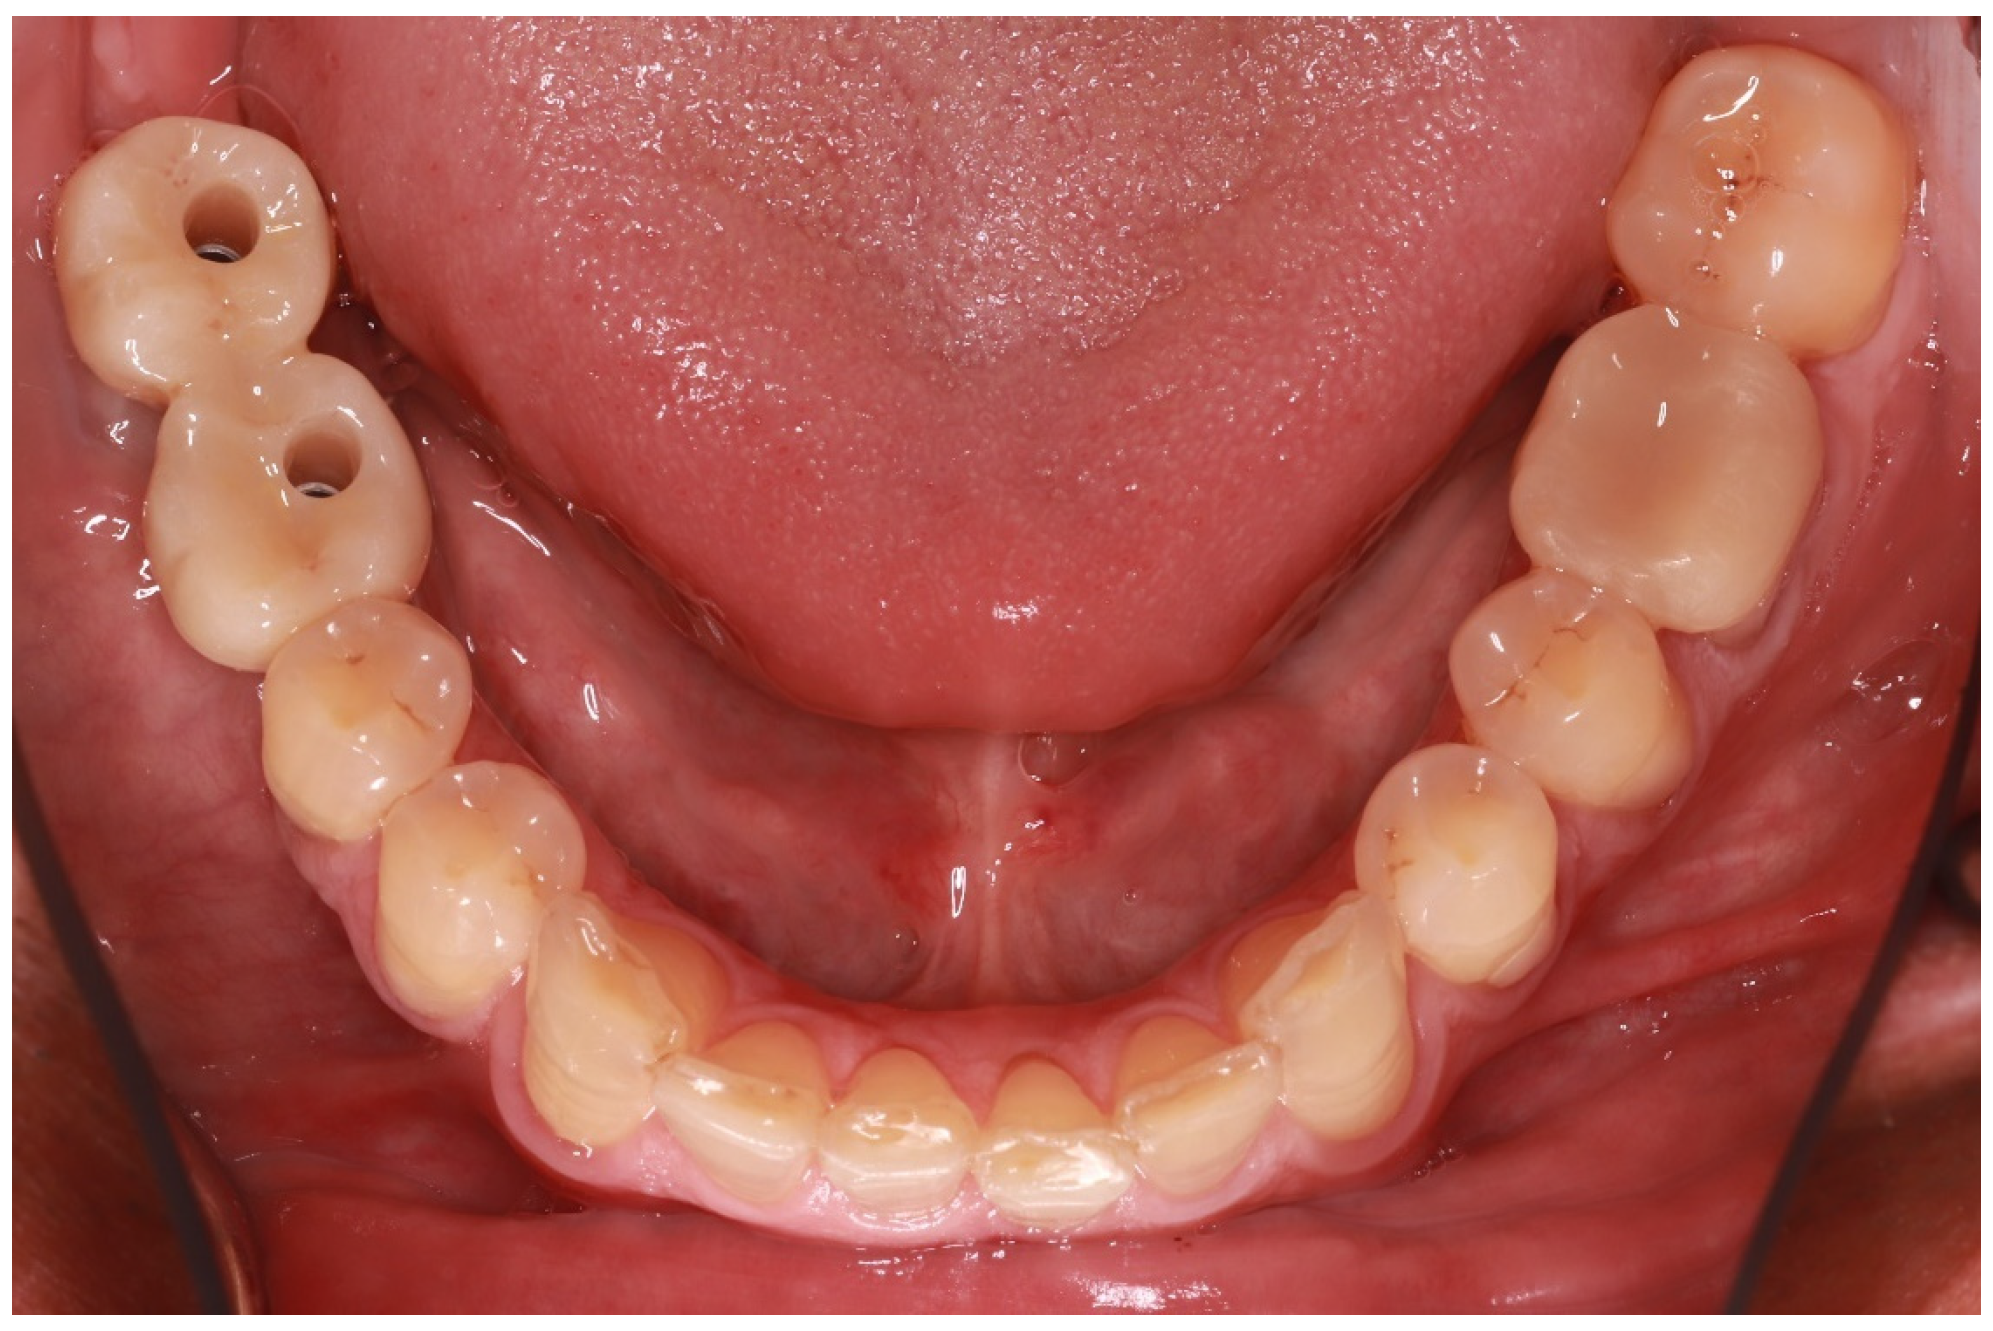

First, existing restorations and decayed tissue were removed. Given that the tooth was restorable, a provisional restoration was placed in order to prevent microleakage and the patient was referred for an endodontic reintervention as the existing root canal treatment was not satisfactory. Enamel presence at a percentage higher than 80% of the tooth circumference substantiated the choice of an endocrown restoration (Figure 2). This type of prosthesis demands the presence of healthy enamel for the adhesive procedures to be more effective [10]. This condition is so crucial that many reports have placed a lack of cervical enamel among the contraindications for endocrown restorations [11].

Figure 2. Adequate enamel presence after removal of previous restorations.